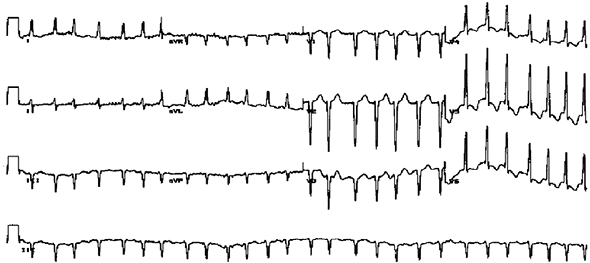

Иллюстрация к книге — Хрупкий мозг. Инсульту не быть? [img_39.jpg]

Типичная электрокардиограмма сердца при мерцательной аритмии